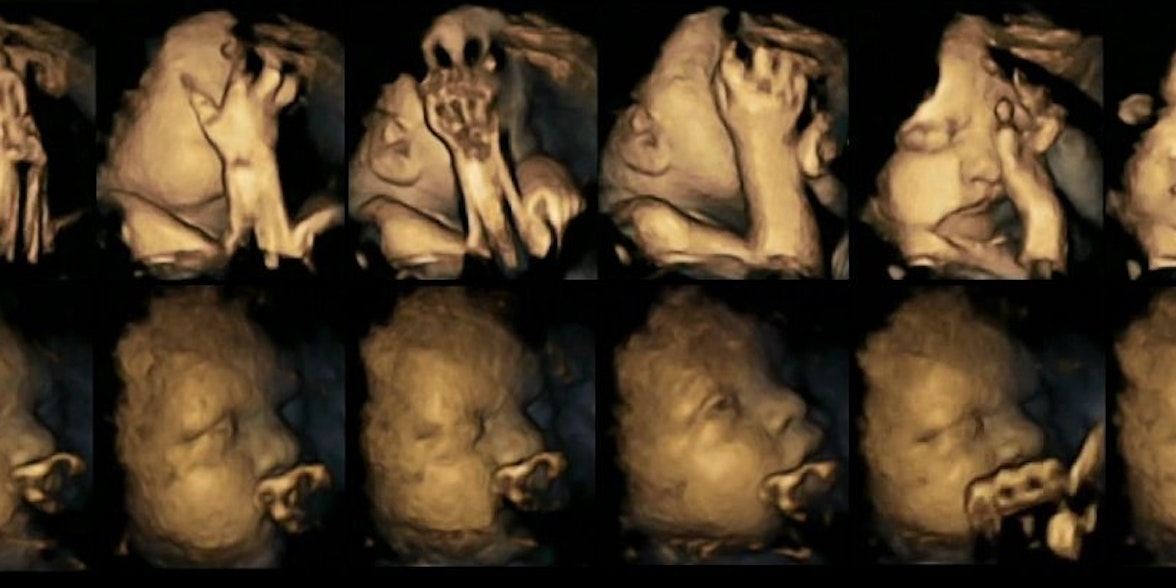

Stress im Uterus: Föten von Raucherinnen (oben im Bild) bewegen häufiger das Gesicht und berühren sich öfter als Ungeborene von Nichtraucherinnen (unten).

Ungeborene, die sehr oft den Mund verziehen, und sich mit ihrer kleinen Hand immer wieder durch das Gesicht fahren: Die 4D-Ultraschall-Bilder von Föten, deren Mütter rauchen, machen die verheerenden Auswirkungen von Zigarettenkonsum in der Schwangerschaft deutlich. Englische Wissenschaftler haben die hochaufgelösten Scans kürzlich in der Fachzeitschrift Acta Paediatrica veröffentlicht. Dass Nikotin schwerwiegende Folgen für das Ungeborene haben kann, ist hinlänglich bekannt. Doch dass die Konsequenzen sich bereits zu einem sehr frühen Zeitpunkt so genau beobachten lassen, ist neu, wie die Forscher der Universitäten Durham und Lancaster in einer Mitteilung erklären.

Das Team um Studienleiterin Dr. Nadja Reissland analysierte für die Pilotstudie achtzig Ultraschallbilder von zwanzig Föten zwischen der 24. und 36. Schwangerschaftswoche. Vier der Mütter waren Raucherinnen, die durchschnittlich 14 Zigaretten pro Tag konsumierten. Die räumlichen, also dreidimensionalen Bilder, der Babys werden durch das Ultraschallgerät in Echtzeit erzeugt: Man spricht deshalb von 4D-Ultraschall oder Live-3D-Ultraschall, weil die Zeit als vierte Komponente hinzukommt. „Die Gesichtsbewegungen der Föten rauchender Mütter und der ungeborenen Babys der Nicht-Raucherinnen unterscheiden sich deutlich“, erklärt Nadja Reissland auf der Homepage der Universität Lancaster.

Die ungeborenen Kinder der Raucherinnen bewegten deutlich öfter den Mund und berührten sich viel häufiger mit den Händen als die der Nichtraucherinnen. Die Wissenschaftler gehen davon aus, dass ihr zentrales Nervensystem, das Bewegungen im Allgemeinen, aber auch Gesichtsbewegungen, steuert, sich nicht so schnell und nicht auf die gleiche Weise entwickelt hat wie das der Föten, deren Mütter nicht rauchen.